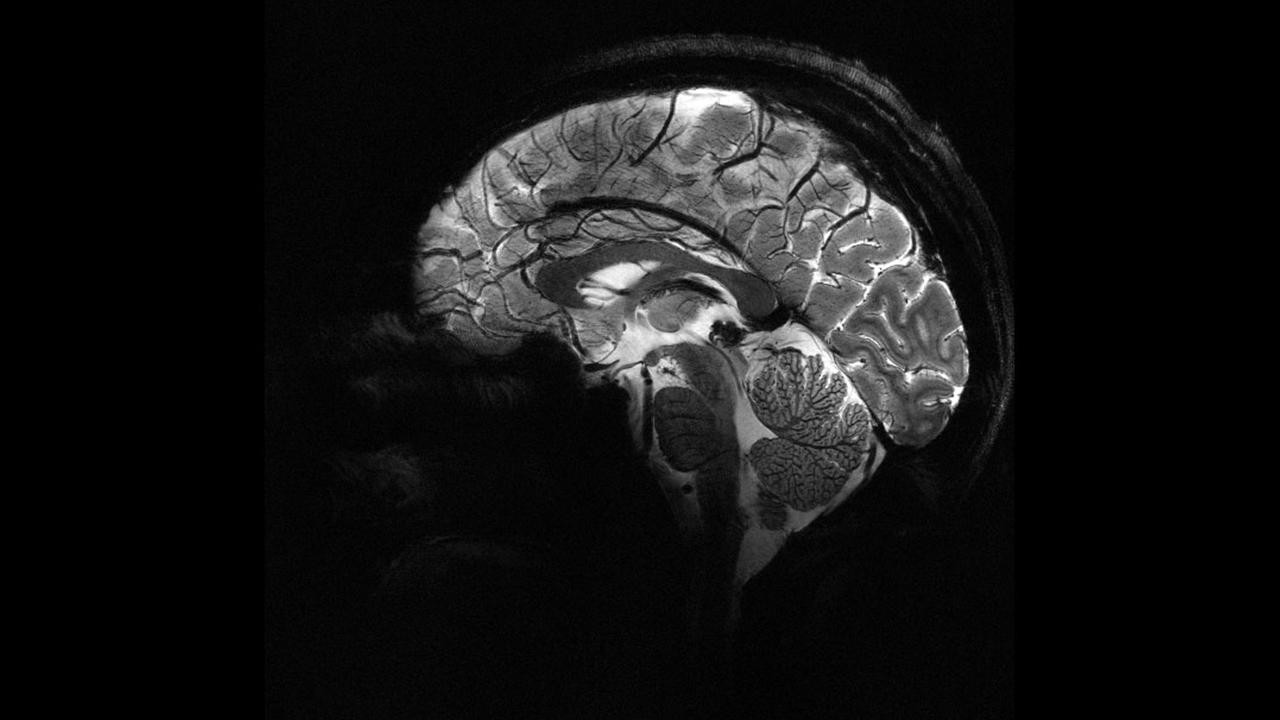

İnsan beyninin en güçlü MRI cihazıyla çekilen en net görüntüsü yayınlandı

Fransa Atom Enerjisi ve Alternatif Enerjiler Kurumu (CEA), dünyanın en güçlü manyetik rezonans görüntüleme (MRI) cihazıyla elde edilen, insan beyninin en net görüntüsünü yayınladı.

CEA'dan yapılan yazılı açıklamada "Iseult" adlı MRI cihazıyla çekilen beyin görüntüsünün 20 yıldan uzun süren bir çalışma sonucu elde edildiği belirtildi.

Yapılan çalışmalar kapsamında MRI cihazının son birkaç ay içerisinde yaklaşık 20 sağlıklı gönüllü üzerinde test edildiği kaydedilen açıklamada, neredeyse 4 dakikada en net beyin görüntüsünün elde edildiği aktarıldı.Açıklamada, 11,7 Tesla manyetik güce sahip Iseult MRI makinesiyle kısa sürede çekilen görüntülerin, hastanelerde yaygın kullanılan cihazlarla elde edilmesinin saatler sürebileceği kaydedildi.

Iseult MRI cihazı ile elde edilen ultra detaylı anatomik bilgilerin, Alzaymır ve Parkinson gibi hastalıkların teşhisinde yardımcı olması bekleniyor.